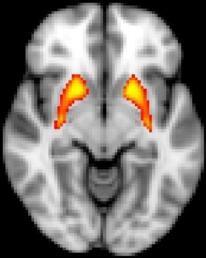

fMRI shows dysfunction in the striatum, which is associated with psychosis risk. Image credit: John Kerns.

Using a feedback-based learning task, lead author Nicole Karcher and colleagues found that people at risk for psychosis are impaired when they need to rely on feedback to learn. More specifically, fMRI brain scans revealed that the striatum failed to activate in people at risk for psychosis when they received feedback, according to study results published online March 24 in Schizophrenia Bulletin.